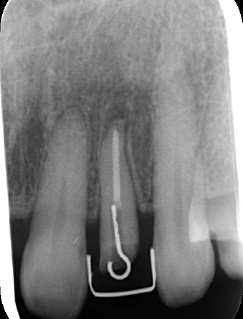

MTM開始直後と、終了後です。フックの位置が変わっているのがわかると思いますが、それが歯が動いた証拠となります。

左は歯を挺出するために装置をつけた直後です。

右は挺出が終わり、コアをセットしたところです。

歯根の位置が歯冠側によっているのがわかります。

| 治療前で歯根が長いのがわかります。歯根がある程度長く無いと、MTMは行えません。 | MTM終了時のもの。フックが上の金属に接している。また根尖に透過像があるが、歯が動いた証拠です。 |